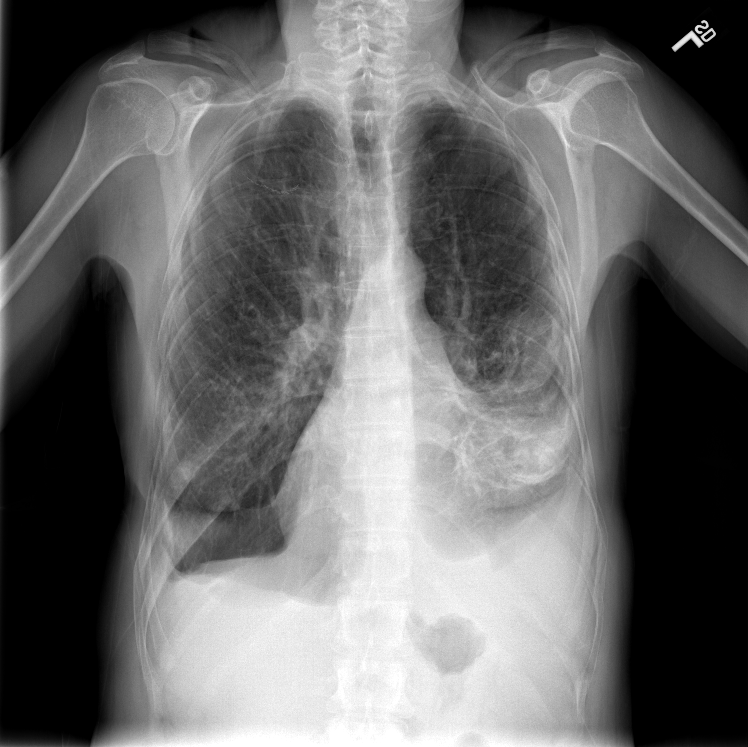

Refer to caption

(a) ”Normal”

(b) ”Bone suppressed”

(c) ”Lung field cropped”

(d) ”Combination”

Fig. 1: One example image (a) of the Indiana chest X-ray dataset from Open-I. The dataset consists of 3125 frontal and lateral images from 3125 patients. We annotated all images with up to eight findings. The pre-processed images are show in (b)-(d). (b) is the bone suppressed image, (c) is cropped to the lung field, and (d) illustrates the combination out of (b) and (c).